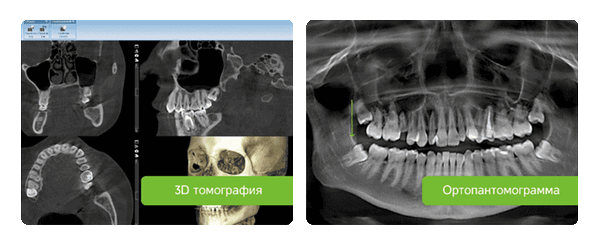

Чтобы оценить состояние зубов и увидеть скрытые дефекты, обычно назначают ортопантомограмму (панорамный снимок) или КТ. Это не прихоть врача, а желание необходимость создать полноценную картину, с учетом всех деталей. К тому же, снимок может выявить воспалительные процессы, которые при осмотре незаметны.

Диагностическая подготовка

Проводится с целью выявить состояние костной ткани и зубных корней, исключить противопоказания. Если вы лечите один зуб, будет достаточно прицельного снимка (рентген). Если врачу необходимо увидеть картину целиком, нужен обзорный снимок (ортопантомограмма). Перед имплантацией вас направят на компьютерную томографию.

Панорамный снимок, КТ. Позволяют увидеть состояние челюстной системы, костной ткани, нервов, носовых пазух. На основании этого врач расписывает план лечения.